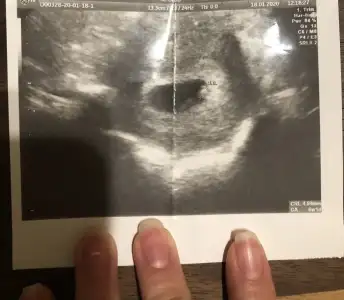

Kızlar merhaba 6+1de bebeği gördük ve kalp atışını duyduk Şükürler olsun ki, ancak benim hesaplamama göre sat a göre 5 gün eksik gözüküyor, yumurtlama dönemimde hiç ilişki olmamıştı geç döllenme olduğu için mi geride gözüküyor acaba, böyle bir durum yaşayan var mı?

• 28CD32A9-09F2-421C-A4A2-6CF8EEB3BDA4.webp

28CD32A9-09F2-421C-A4A2-6CF8EEB3BDA4.webp

37,4 KB · Görüntüleme: 63

Benim de 5 gün önce canm sat a göre .ilişki günü de belli yumurtlama zamanı. Bilmiyorum bende tedirginim biraz. Seninki geç döllenme olabilir.